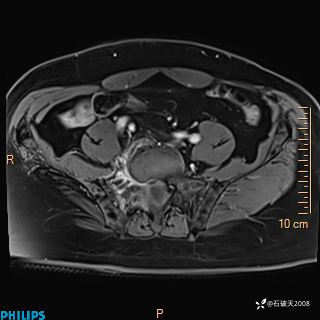

2023年3月份MRI影像

增强轴位